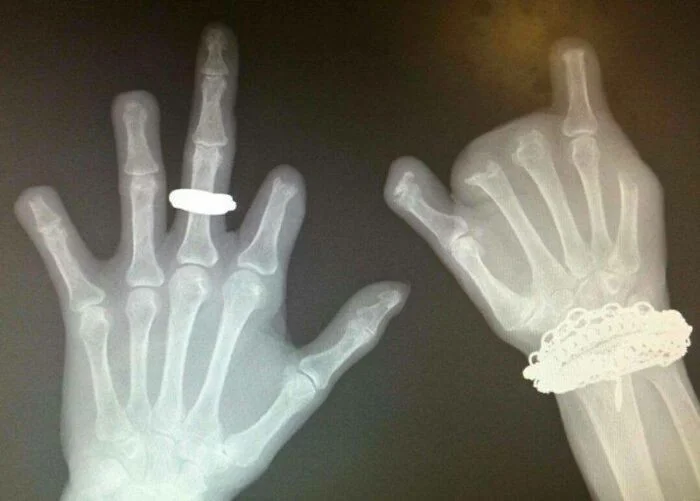

12. Рентген пациента, который долгое время жевал и обгрызал пальцы до кости

Это привело к тяжёлым бактериальным инфекциям и многократным ампутациям.